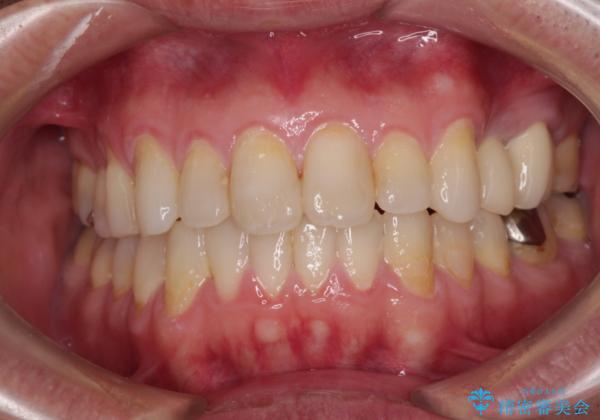

内側に転位した歯とボロボロのむし歯 インビザラインによる矯正治療とむし歯治療

- ボロボロのむし歯とデコボコの歯列を気にして来院された患者様です。

ボロボロとなっていた歯は抜歯が必要な状態でしたが、舌側転位している歯を移動させることで抜歯スペースを埋めることができるため、矯正治療により歯列を整えることとしました。

舌側転位の改善にインビザラインを用いるのはやや難易度が高くなりますが、前歯部のデコボコは軽度であったため、インビザラインによる矯正治療を行うこととしました。

矯正治療後には抜歯が必要な歯に隣接してむし歯となっていた歯をオールセラミッククラウンにて補綴治療を行うこととしました。